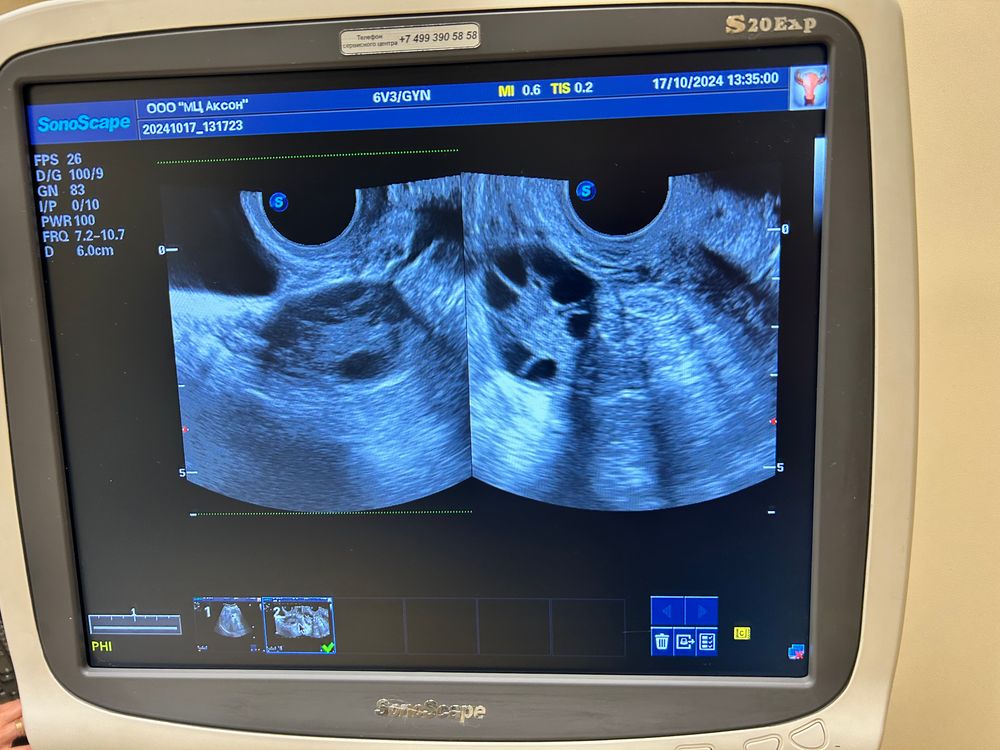

Девочки , подскажите пожалуйста , была на фолликулометрии сказали овуляции нет и как поняла не будет

один гинеколог говорит что нужна стимуляция , другая говорит что овуляция есть и даже желтое тело и что стимуляция не нужна. Последнее уже на 15 день цикла сделано .

Зачем вам стимуляция? Если у вас хорошие узи и растет доминантный фолликул? Эндометрий хороший на момент последнего узи фолликул был 13мм ( в сутки ростет в двое) от 20 до 25 лопается и случается овуляция!

У вас картина 2 фазы, т.е.О была, есть ЖТ с кровотоком. Э̥т̥о̥ в̥е̥р̥х̥н̥е̥е̥ У̥З̥И̥.

Нижнее не понятное какое то.

Виктория , вот верхнее узи было при задержки сделано , по нему врач видит желтое тело и овуляцию , и по этому узи другой врач говорит делать стимуляцию надо

Но сейчас по узи ее нет - на последнем узи

Виктория , первое (верхнее) при задержке , точно не помню ну где то 25-30 дней задержки было , а последнее (нижнее) после месячных на 15дц

Anna Anna, если я правильно поняла, то у вас очень поздние О и длиннющая 2 фаза? Тогда Г права - надо цикл взять под контроль и провести стимуляцию, наличие своей О не повод не стимулироваться. На 15 ДЦ толком нет и ДФ, даже 13 мм - мало, а задержки 30 дней вообще ненормально.